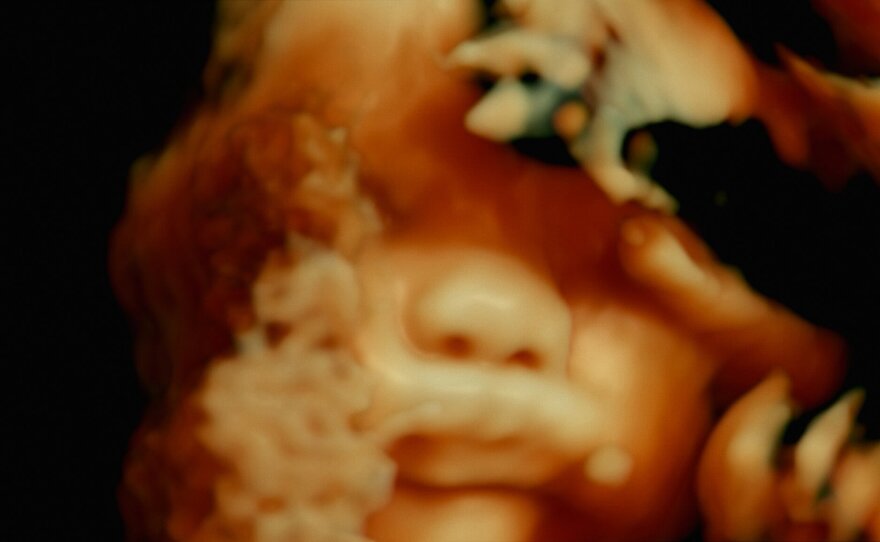

A human fetus as seen in the documentary "De Humani Corporis Fabrica."

I have to say that the film fascinated and annoyed me in equal parts. Some of the medical footage is absolutely amazing and serves up landscapes that the 1966 film "Fantastic Voyage" could only imagine. We travel inside intestines and hearts, detect a baby's features through sonograms, see twisted vertebrae in x-rays, and are dazzled by beautiful slides of dissections. These are all images that we don't often have access to, and we can marvel at the technology that permits us to see the body in such vivid detail.